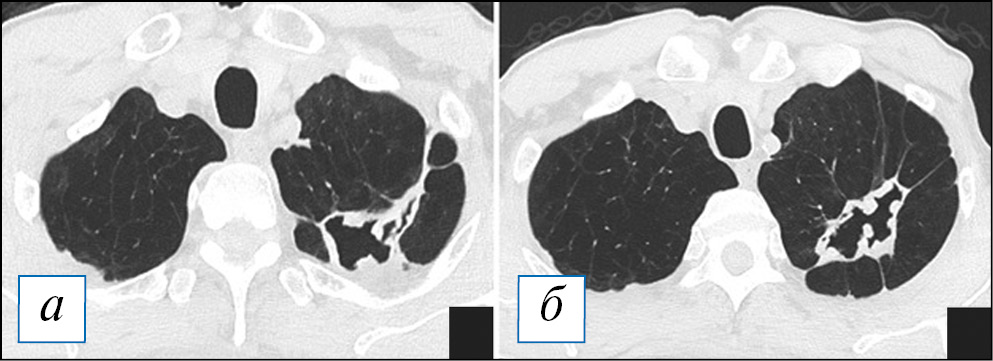

По данным компьютерной томографии (КТ) у пациентов с очаговой пневмонией обнаруживают небольшие перибронхиальные очаги, обычно солидного типа или с нечеткими контурами за счет ободка «матового стекла», при бронхиолите — мелкие очажки в виде симптома «дерева с набухшими почками», при этом прилежащие стенки бронхов могут быть утолщены и уплотнены за счет воспалительного процесса. Возможно слияние очагов, которое не принимает характера обширной инфильтрации. При пневмонии контуры очагов менее четкие из-за преобладания экссудативного воспалительного компонента, что отличает ее от бронхиолита [38]. Важным симптомом бронхогенного процесса можно рассматривать наличие патологического содержимого в просвете бронхов, что представлено слизистым или гнойным содержимым (рис. 1). На традиционных рентгенограммах изменения из-за малого размера могут быть вовсе не заметны или представлять собой мелкие очаги/ограниченную диссеминацию; отмечается локальное усиление/обогащение легочного рисунка, преобладающее в какой-то одной доли легкого.

Рис. 1. Компьютерная томография органов грудной клетки в аксиальной проекции (а–г). Двусторонняя сливная бронхопневмония и бронхиолит у пациента с наличием в мокроте S. pneumoniae и S. aureus в значимых титрах. С обеих сторон, больше в нижних долях, на фоне обтурации просветов крупных бронхов патологическим содержимым (стрелки) имеются перибронхиальные разнокалиберные очаги, в том числе по типу симптома «дерева с набухшими почками» (рамка). В верхних отделах данные очаги сливаются в инфильтраты. [Изображения из архива авторов]. / Fig. 1. Chest CT, axial projection (а–г). Bilateral bronchopneumonia and bronchiolitis (with the etiology of S. pneumoniae and S. aureus confirmed by a sputum test). On both sides, more in the lower lobes against the background of bronchial sputum obturation (arrows), there are peribronchial nodules of various sizes, including a “tree in bud” sign (frame). In the upper lungs areas the nodules formed infiltrates. [Images from the authors’ archive].